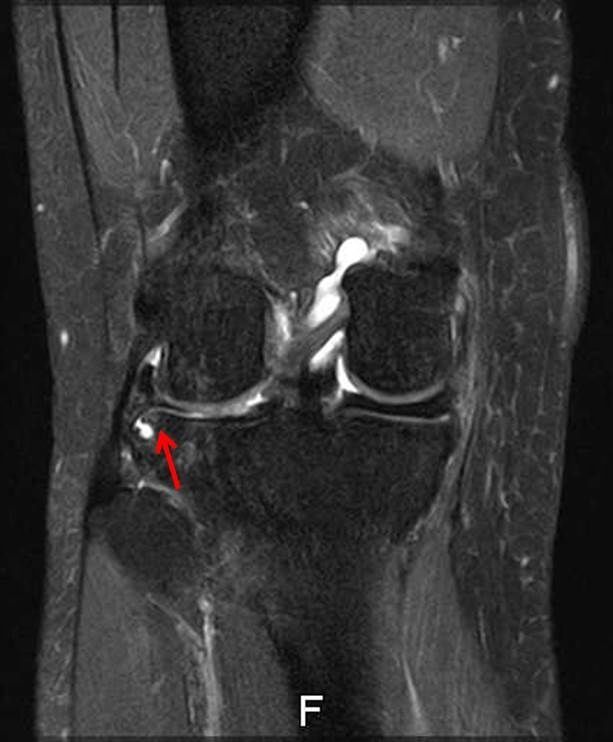

画像所見

| レントゲン | MRI | |

| 骨傷なし、骨棘あり Kellgren-Lawrence分類gradeⅡ | 外側半月板のフラップ損傷あり 骨損傷あり | |